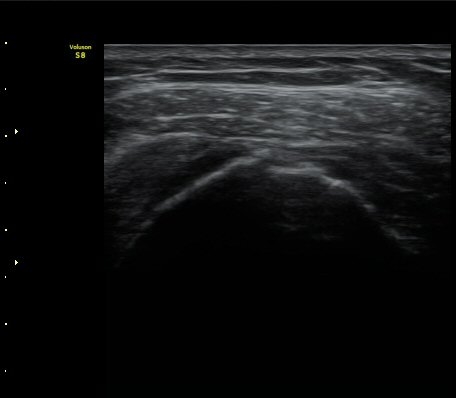

¾î±ú ±Ø»ó°Ç ÃÊÀ½ÆÄ°Ë»ó ±Ø»ó°Ç ºÎÂøºÎ°¡ °üÂûµÇÁö ¾Ê°í ±ÙÀ§ºÎ·Î ´ç°ÜÁ® ÀÖ´Ù(±×¸² 1, 2).

±Ø»ó°Ç Ⱦ´Ü¸é°Ë»ç»ó »ó¿Ï°ñµÎ¸¦ µ¤°í ÀÖ¾î¾ßÇÒ ±Ø»ó°ÇÀÌ º¸ÀÌÁö ¾Ê°í Á¡¾×³¶ÀÌ ÆíÆòÇϰÔ

³»·Á ¾É¾Æ º¸ÀδÙ(±×¸² 3).